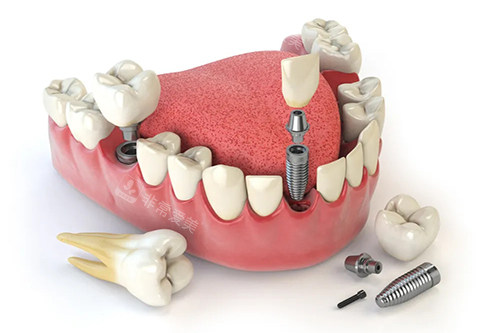

牙齿种植牙模型卡通示意图

牙齿种植卡通示意图